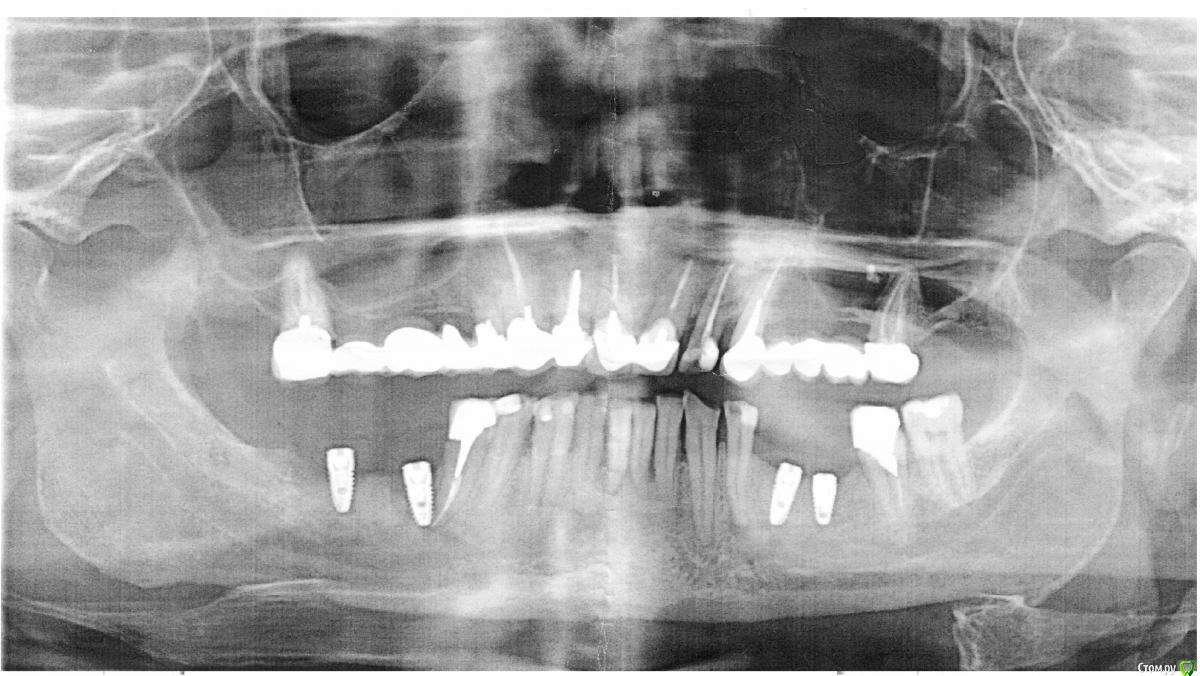

Колосс Опубликовано 6 сентября, 2018 Поделиться Опубликовано 6 сентября, 2018 (изменено) Прошу совета профессионалов. 4 месяца назад мне установили на нижней челюсти 4 импланта, корейцы.2 справа и 2 слева. Справа были сложные. один в удаленный зуб, второй, кость была слишком пористая и были какие то сложности. Был в другой клинике. Сказали, что в обоих справа гной и они не приживутся. Подскажите, это развод на деньги или действительно мои дела так плохи? Изменено 6 сентября, 2018 пользователем Колосс Ссылка на комментарий

red_butler Опубликовано 6 сентября, 2018 Поделиться Опубликовано 6 сентября, 2018 Можно поподробнее, почему удалять?Что с ними не так?Вокруг имплантов нет кости Ссылка на комментарий

Bier Опубликовано 14 сентября, 2018 Поделиться Опубликовано 14 сентября, 2018 Подскажите пожалуйста, как Вы это определили.Мне для аргументации разговора с хирургом.Хирург говорит что будет определено только при вскрытии. Я как не специалист ничего не вижу на снимке.Может так получиться что установят коронку и она вскорости вывалится к моему ужасу. И что потом делать после того как имплант удалят?они сильно выстоят над костным гребнем (справа) а слева очень неудачный наклон, но возможно ортопед справится.Но вы не сможете спорить со своим врачом, у него в любом случае глубина знаний гораздо больше, если он не согласен, то найдет контрдоводы.Чем больше врачей ставят имплантаты тем больше таких случаев. 1 Ссылка на комментарий